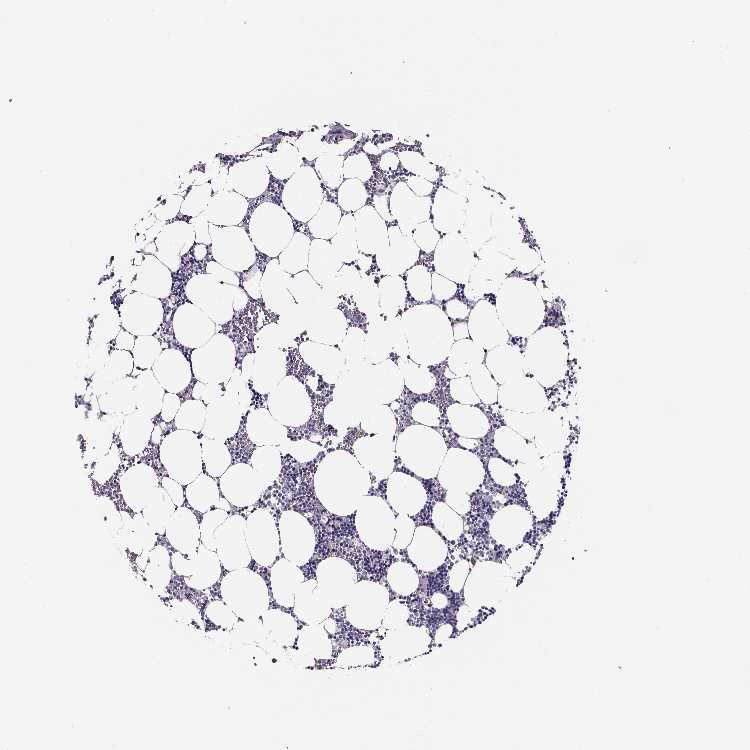

BONE MARROW - Antibody stainingi

Antibody staining in the annotated cell types in the current human tissue is reported as not detected, low, medium, or high, based on conventional immunohistochemistry profiling in selected tissues. This score is based on the combination of the staining intensity and fraction of stained cells.

Each image is clickable and will lead to virtual microscopy that enables deeper exploration of all samples and also displays staining intensity scores, fraction scores and subcellular localization as well as patient and tissue information for each sample.

Antibody HPA031422Antibody HPA031425

Hematopoietic cells Not detectedLow